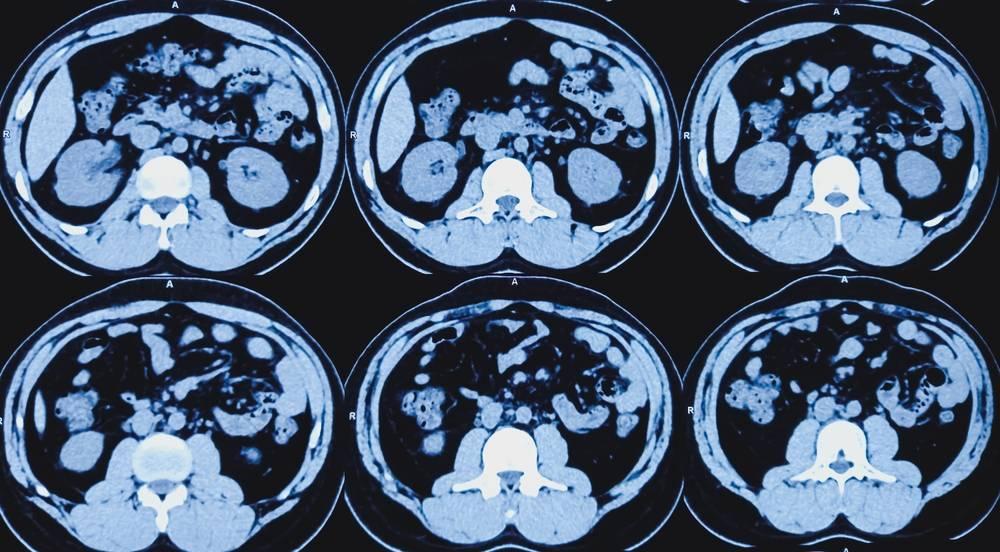

Computed Tomography (CT) scans, also known as CAT scans, play a crucial role in the field of oncology. These advanced imaging techniques provide valuable insights for cancer detection, staging, and treatment planning. But how exactly do CT scans contribute to cancer care?

CT scans utilize X-rays from multiple angles to create detailed, three-dimensional images of the body’s internal structures. This technology allows oncologists to:

The ability to visualize abnormal growths and assess their size, shape, and relationship to surrounding tissues makes CT scans an indispensable tool in modern cancer management.

As the patient lies on a table that moves through a doughnut-shaped machine, X-ray beams rotate around the body, capturing cross-sectional images. A computer then combines these images to create a detailed 3D representation of the scanned area.

A CT scan takes pictures of the inside of the body using x-rays taken from many angles. A computer combines these pictures into a detailed, 3-dimensional image. This image will show abnormal areas and any tumors.

Areas commonly scanned for cancer include the head, neck, chest, abdomen, pelvis, or limbs. A “total body” CT scan generally includes at least the chest, abdomen, and pelvis. Doctors often use this is for cancer staging.